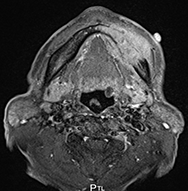

図❸ 下顎左側歯肉部から下顎骨にかけて、骨破壊を伴う腫瘤形成を認める